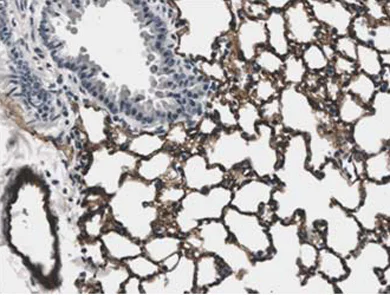

Immunohistochemistry (Formalin/PFA-fixed paraffin-embedded sections) - Anti-CD31 antibody [RM0032-1D12] - BSA and Azide free (AB56299)

ab56299 at 1/400 staining CD31 in LPS treated mouse lung tissue section by Immunohistochemistry (Formalin/PFA fixed paraffin-embedded sections).